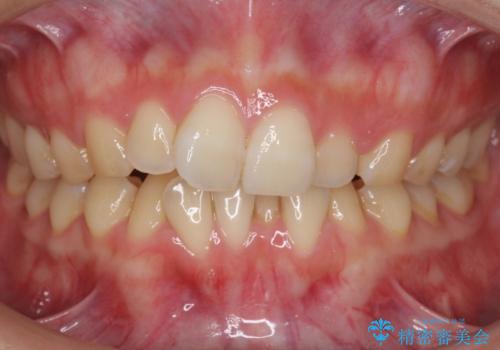

[40代男性・受け口] 下のみ抜歯の矯正治療

- 前歯の反対咬合を主訴に来院。

歯の数を揃えて下の前歯を下げるため、下を二本抜歯して並べました。

時間は多少かかりましたが、治療結果には大変満足していただきました。

40代男性ということもあり、なかなか下の臼歯が動かず隙間を閉じるのが大変でしたが、無事治療を終えることができました。

現在、すべての詰め物のやりかえを行っています。